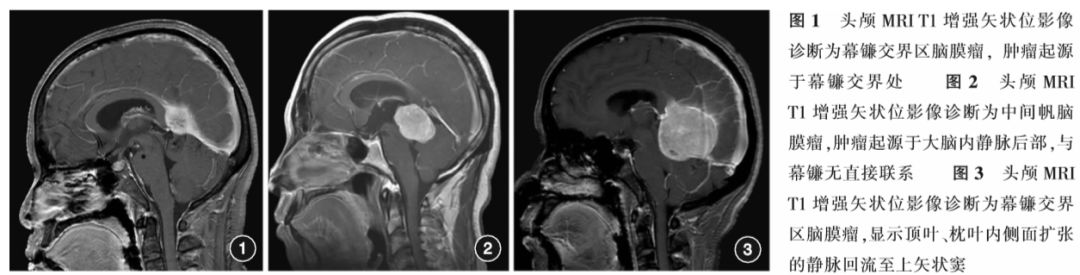

21例患者中,12例肿瘤位于大脑大静脉后下方,5例位于静脉的前上方,3例位于静脉的侧方,1例包裹静脉。4例肿瘤与小脑幕、5例肿瘤与幕镰交界区、5例肿瘤与直窦下表面接触且接触面广泛(图1),4例肿瘤虽与直窦或大脑镰有紧密接触,但更大接触面在大脑大静脉上;其余3例肿瘤与幕镰未直接接触,其中2例肿瘤与大脑大静脉和大脑内静脉后段、1例与大脑内静脉后段及松果体紧密接触(图2)。肿瘤与幕镰有直接接触的18例患者中,MRI显示12例有幕镰强化,表现为接触区幕镰毛糙性增强,5例伴有幕镰脑膜尾征。MRV显示12例大脑大静脉和直窦未能显影,3例大脑大静脉有狭窄的表现,3例静脉有移位但显影无明显异常。12例大脑大静脉未能显影的患者中,5例在顶叶内侧面可见扩张的静脉,考虑为静脉性侧支循环(图3)。结合CT检查,8例可见移位的松果体,位于肿瘤的前部。15例合并有脑积水,脑室轻度至中度扩大。